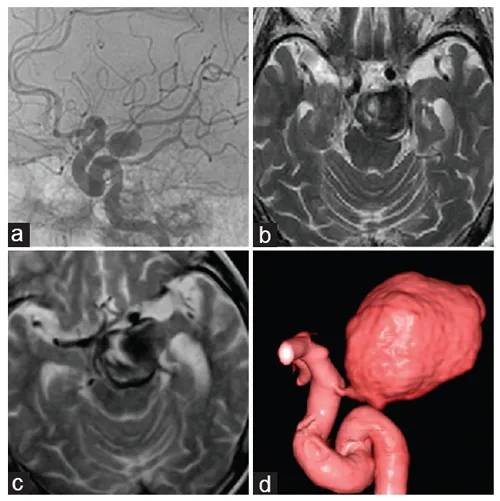

65岁女士,有左侧面部神经瘫痪和头晕1月,随后出现吞咽障碍和声带麻痹,随后就诊,影像检查显示3厘米大小的占位,考虑主要是血栓形成的VA椎动脉瘤,包括PICA(图1)。巴特朗菲教授为其进行手术,术后动脉瘤血栓形成的部分几乎完全切除,无因手术造成的神经功能缺损。

图1(A-C):术前磁共振扫描显示部分血栓形成的VA-PICA动脉瘤,并压迫脑干。

图1D:术前左侧VA造影显示大量血栓形成的VA-PICA动脉瘤的灌注部分(箭头)。图1E:术前左侧VA血管造影,VA-PICA动脉瘤合并巨大血栓形成,显示动脉瘤灌注部分(星形)和不同直径的左侧VA(箭头)和PICA(双箭头)。

图1F:磁共振血管造影显示VA-PICA动脉瘤部分血栓形成(箭头)。图1G:CT显示动脉瘤的血栓形成及部分钙化(箭头)。

病人在手术当天即神志清楚,没有出现新发的神经功能缺损。在术后第一天的检查中,未发现局部或远端梗死和吻合口再出血(图2A-B)。MR显示脑干压迫效应解除(图2C-和D),术后血管造影显示吻合的PICA充盈良好、血流通畅(图2E-F)。术后恢复顺利,无术后并发症。经过7年的随访,声带麻痹已痊愈,生活正常。

图2A-B:CT显示动脉瘤囊切除和VA-PICA吻合术后,远外侧入路的骨磨除部分。

图2C-D:术后MR显示动脉瘤体切除。

图2E-F:术后血管造影显示成功的VA-PICA吻合术,不同直径的VA(星号)和PICA(双箭头)以及远端VA上的永久夹闭(单箭头)。